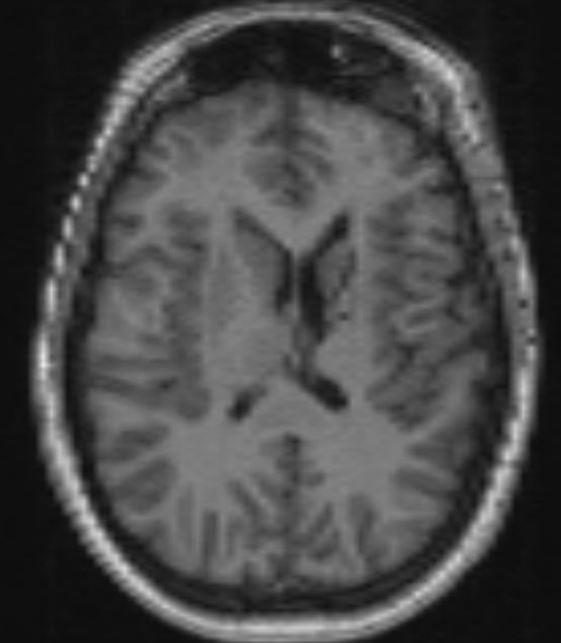

The structural correlates of the above EEG findings appear below. There is enlargement of the left-ventricular system, atrophy of the head, body and tail of the caudate nucleus and the left hemisphere appears modestly smaller in size than the right, most evident on axial sequences. The MRI was done while the patient was quite restless. As you can see from these pictures, the left occipital cortex and the left thalamus do not demonstrate any structural correlate to the asymmetry of alpha rhythms. However, we know from the EEG that the left hemisphere is markedly dysfunctional. Unsurprisingly, on functional MRI scans language is represented in the right hemisphere.